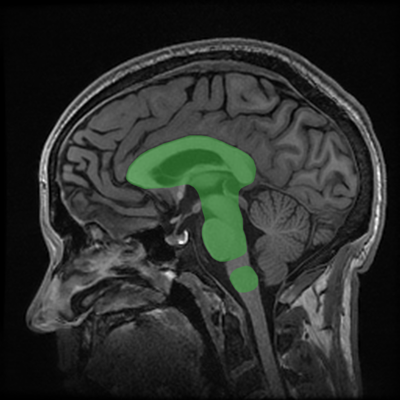

Body CT: Back to Basics and Beyond is a program consisting of 30 state-of-the-art lectures covering many of the most important topics in body CT today, ranging from scan protocols to study design to study interpretation. Anatomical areas addressed are the major organs, particularly focusing on the chest, heart, liver, and colon. Pitfalls and potential sources of error are featured in each lecture. Technical aspects of the exam include the importance of CT dose reduction, for example. We hope you enjoy the program and appreciate any comments or suggestions for future editions.